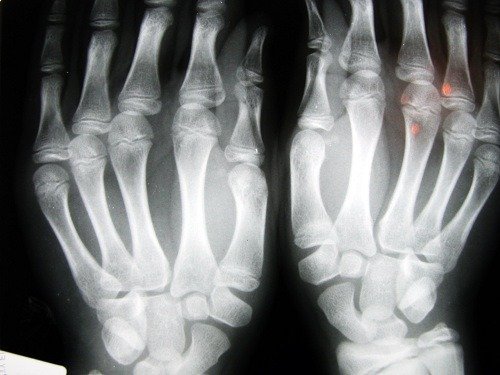

Остеопорозата е костно заболяване водещо до намаляване на костната плътност. При него костите са силно порести. Повишавайки големината на вътрешните клетки на костите, те стават по-крехки и се чупят много по-лесно.

Обикновено се наблюдават счупвания в областта на китките и бедрата. Бедрените фрактури са най-сериозните, тъй като изискват спешна хирургична намеса и оказват значителни последствия върху здравето на пациента.